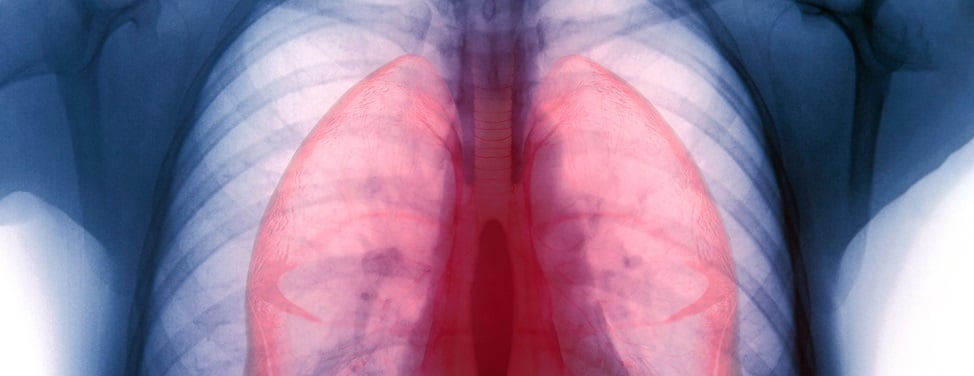

That night at UCSF Benioff Children's Hospital San Francisco, Allison met with Dr. Jeffrey Fineman, a pediatric cardiac critical care specialist who directs the Pediatric Pulmonary Hypertension Program. The next day, Allison underwent a cardiac catheterization procedure, which confirmed a diagnosis of pulmonary hypertension (PH).

"I was told later that I nearly had cardiac arrest during the catheterization," Allison recalls. "My pulmonary hypertension was considered idiopathic, meaning there was no known cause. They started treating me aggressively with medications, including Remodulin delivered subcutaneously—which is basically like an insulin pump. They also used tadalafil and ambrisentan, which is an endothelin receptor blocker. All of those drugs work to open up the pulmonary arteries but in different ways."

"Allison's pulmonary blood pressure has dropped to almost normal, and her heart functions extremely well," he says.